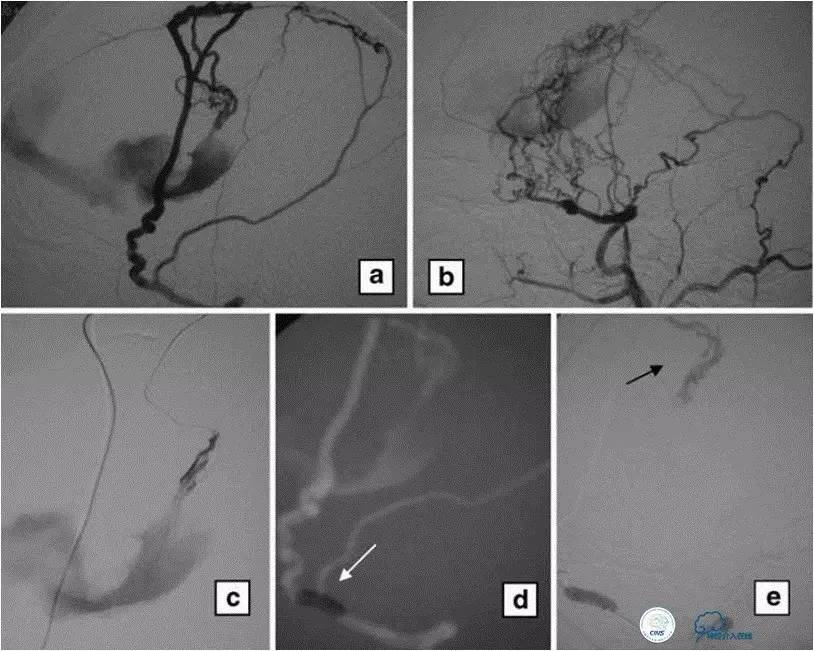

海绵窦区DAVF,颈内外均参与供血。

采用净买入路,经岩下窦栓塞。

首先放入少量弹簧圈,给Onyx提供框架。

开始注入Onyx时,在颈内动脉内放入保护球囊,防止意外进入颈内动脉内。

栓塞后胶的透视影像。

最终结果,DAVF完全消失。

文献中图片,经颈外动脉栓塞,在椎动脉内放置保护球囊,防止通过脑膜后动脉逆向栓塞椎动脉。

参考:Endovascular treatment of high-risk tentorialdural arteriovenousfistulas: clinical outcomes. Neuoradiology2009;51:103-111.